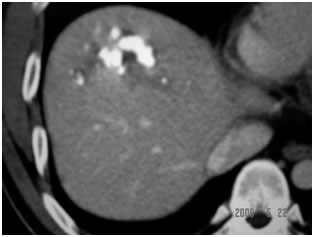

CT Scan showing Lipoidol uptake in segment VIII